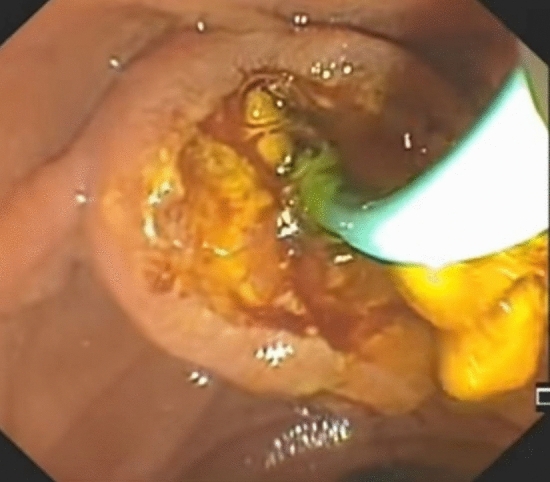

According to usual procedure, a laparoscopic cholecystectomy was performed with the standard four trocars technique. To avoid intestinal distension with air during ERCP, LC was started first. The cystic artery was located, clipped, and cut after the Calot’s triangle was dissected. The cystic duct was clipped high toward the GB, and a tiny incision was made near the clip for introduction of the cholangio-catheter to confirm the presence of CBD stones. A cholangio-catheter (4 Fr. Ureteric catheter) was used to catheterize the cystic duct (Fig. 2), and IOC was obtained following injection of 10 cc of diluted urografin utilizing a C-arm X-ray. The decision to perform IO-ERCP was made when the IOC revealed the presence of a CBDS or when the anatomy of the CBD was suspicious for the presence of a CBDS. A 0.035-inch guidewire was inserted into the cystic duct and progressed down past the sphincter of Oddi and into the duodenum by the surgeon. The duodenoscope was placed by the surgeon with the patient remaining in the supine position and advanced to the second portion of the duodenum, where the guidewire was encountered upon detection of the papilla (rendezvous technique) and was used to guide cannulation of the CBD using a sphincterotome. Endoscopic retrograde cholangiography (ERCP) was performed using diluted urografin given through the sphincterotome. A sphincterotomy was performed when a CBDS was discovered. The CBDS was subsequently removed using a retrieval Fogarty balloon (8.5 or 11.5 mm) (Fig. 3). After that, a completion cholangiography was performed to ensure that the CBD was free of stones. Care was taken to remove all gas from the stomach at the end of each ERCP to make the LC easier to complete.